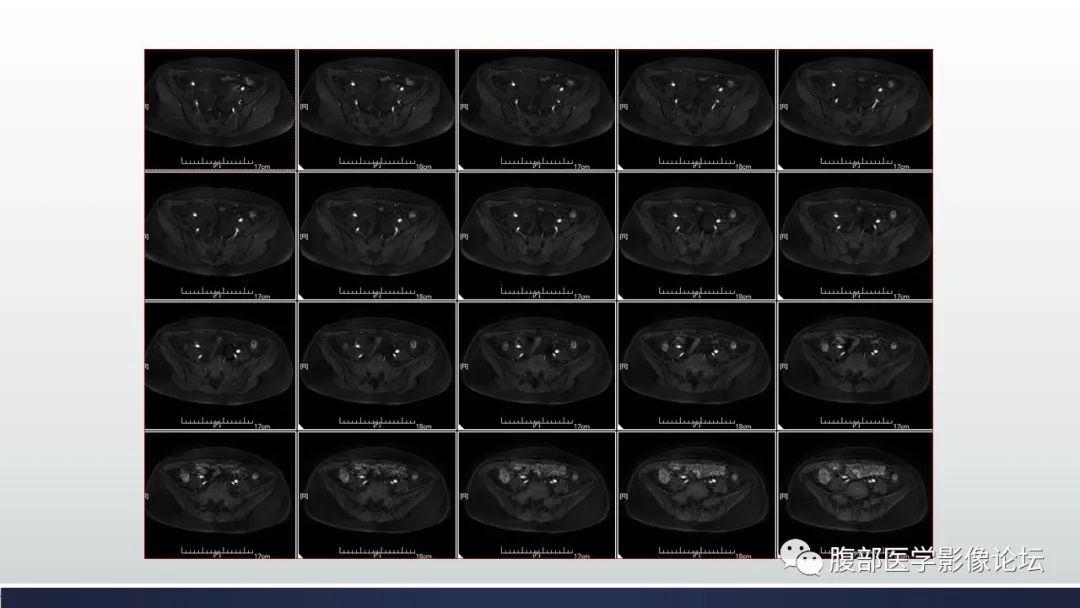

【病例】子宫内膜透明细胞癌1例MR-5

【病例】子宫内膜透明细胞癌1例MR-6

【病例】子宫内膜透明细胞癌1例MR-7

【病例】子宫内膜透明细胞癌1例MR-8